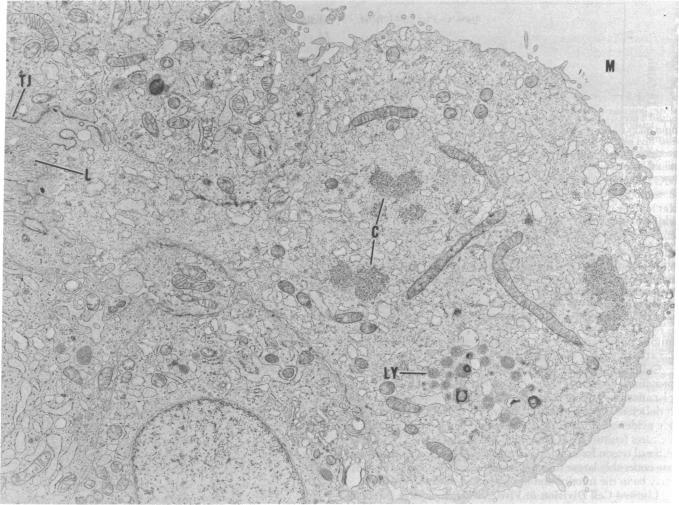

We have been investigating the extent to which separated thyroid follicles in suspension culture, free of endothelium and fibroblasts, have the properties of follicles in vivo. To test whether thyrotropin (TSH) can cause thyroid epithelial cells to undergo mitosis, preparations of follicles suspended in Coon's modified F-12 medium with 0.5% calf serum were incubated with 10 milliunits of impure or pure TSH per ml. Three results were obtained: (i) TSH preparations stimulated the incorporation of [3H]thymidine into cell nuclei; (ii) mitotic figures were induced and they had the same characteristic ultrastructural features as those observed in vivo; and (iii) the cell number doubled in the course of 3 days of exposure to TSH. The results suggest that TSH is a mitogen for the principal thyroid epithelial celland that other substances found in the usual impure TSH preparations are not necessary for the mitogenic activity. It can act in the absence of nonfollicular cells. The initial multiplication rates are similar to those in vivo. The cells do not have to spread to divide in contrast to the requirement for spreading in the case of fibroblasts.

我们一直在研究悬浮培养中分离出的、无内皮细胞和成纤维细胞的甲状腺滤泡在多大程度上具有体内滤泡的特性。为了测试促甲状腺激素(TSH)是否能使甲状腺上皮细胞进行有丝分裂,将悬浮于含0.5%小牛血清的库恩改良F-12培养基中的滤泡制剂与每毫升10毫单位的不纯或纯TSH一起孵育。得到了三个结果:(i)TSH制剂刺激[3H]胸腺嘧啶核苷掺入细胞核;(ii)诱导出有丝分裂图像,且它们具有与体内观察到的相同的特征性超微结构特征;(iii)在暴露于TSH的3天过程中细胞数量翻倍。结果表明,TSH是主要甲状腺上皮细胞的有丝分裂原,并且通常不纯的TSH制剂中发现的其他物质对于有丝分裂活性不是必需的。它可以在无非滤泡细胞的情况下发挥作用。最初的增殖率与体内相似。与成纤维细胞分裂需要铺展不同,这些细胞不需要铺展就能分裂。